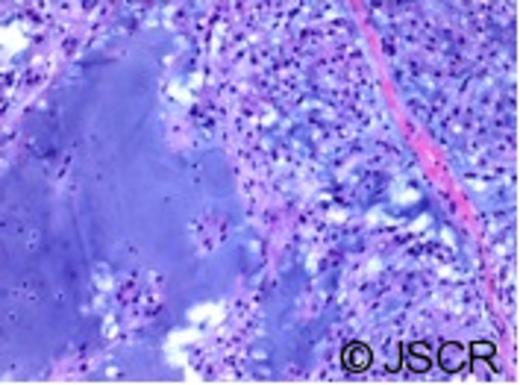

Contrast enhanced CT revealed some residual enhancement along the clival bone and left retropharyngeal area. The patient was reviewed at the multidisciplinary tumour board and with neurosurgery. She was diagnosed as having a recurrence of the chordoma following surgical pathway implantation. She underwent left salvage modified radical neck dissection (levels II-V) with sacrifice of the internal jugular vein and sternocleidomastoid, with preservation of the accessory nerve. Histopathology confirmed the presence of dermal fibrosis within the original neck scar. The left neck mass was composed of nests of large physaliferous cells with vacuolated cytoplasm surrounded by abundant myxoid material, consistent with chordoma (Figure 2). Surgical margins were clear. Lymph nodes were negative for malignancy. On immunohistochemistry, the tumour stained for low molecular weight keratin, high molecular weight keratin and epithelial membrane antigen. Stain for S100 protein was negative.

Histological appearance of chordoma. The tumour is composed of lobules of large cells with vacuolated cytoplasm admixed with a myxoid stroma.